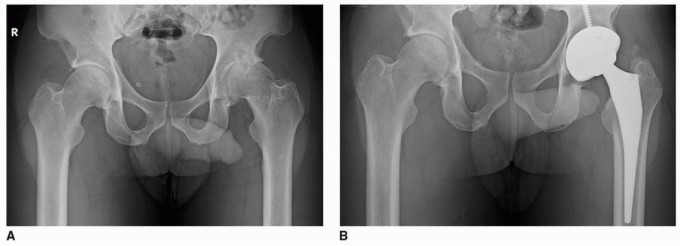

بروز الحُق (Protrusio Acetabuli)

وهي حالة تتسم بانغماس رأس عظم الفخذ والحُق في الحوض بشكل غير طبيعي. تتطلب هذه الحالات تخطيطًا دقيقًا وتقنيات جراحية متخصصة، حيث يفضل الأستاذ الدكتور محمد هطيف استخدام التثبيت بدون أسمنت لتعزيز الاندماج العظمي في العظم المتبقي.

النخر العظمي (Osteonecrosis)

يحدث النخر العظمي عندما يموت جزء من العظم بسبب نقص إمدادات الدم. عندما يؤثر هذا على رأس عظم الفخذ أو الحُق، يمكن أن يؤدي إلى انهيار المفصل وألم شديد. يوفر التثبيت بدون أسمنت حلاً ممتازًا في هذه الحالات، حيث يدعم نمو العظم الصحي حول الغرسة.